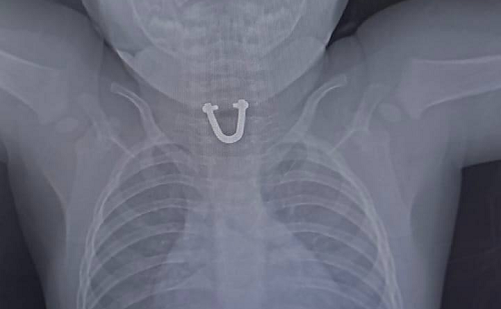

Инородным предметом оказалась маленькая деталь от замка женской сумки В Новороссийске врачи спасли 8-месячного ребенка, проглотившего железную деталь в форме подковы. Родители заметили неладное, когда ребенок начал отказываться от еды и капризничать. В больнице младенцу сделали рентген. Выяснилось, что в его пищеводе находится посторонний предмет. Медики должны были действовать быстро, так как «подковка» могла спровоцировать образование пролежней и даже появление отверстий в пищеводе, что могло привести к смерти. С помощью щипца, известного как «крысиный зуб», удалось захватить «подковку». Вероятно, что инородным предметом оказалась маленькая деталь от замка женской сумки, рассказали в пресс-службе ГБУЗ ГБ №1.

Фото: t.me/gorbolnica1nvrsk

В Новороссийске врачи спасли 8-месячного ребенка, проглотившего железную деталь в форме подковы. Родители заметили неладное, когда ребенок начал отказываться от еды и капризничать. В больнице младенцу сделали рентген. Выяснилось, что в его пищеводе находится посторонний предмет.

Медики должны были действовать быстро, так как «подковка» могла спровоцировать образование пролежней и даже появление отверстий в пищеводе, что могло привести к смерти.

С помощью щипца, известного как «крысиный зуб», удалось захватить «подковку». Вероятно, что инородным предметом оказалась маленькая деталь от замка женской сумки, рассказали в пресс-службе ГБУЗ ГБ №1.